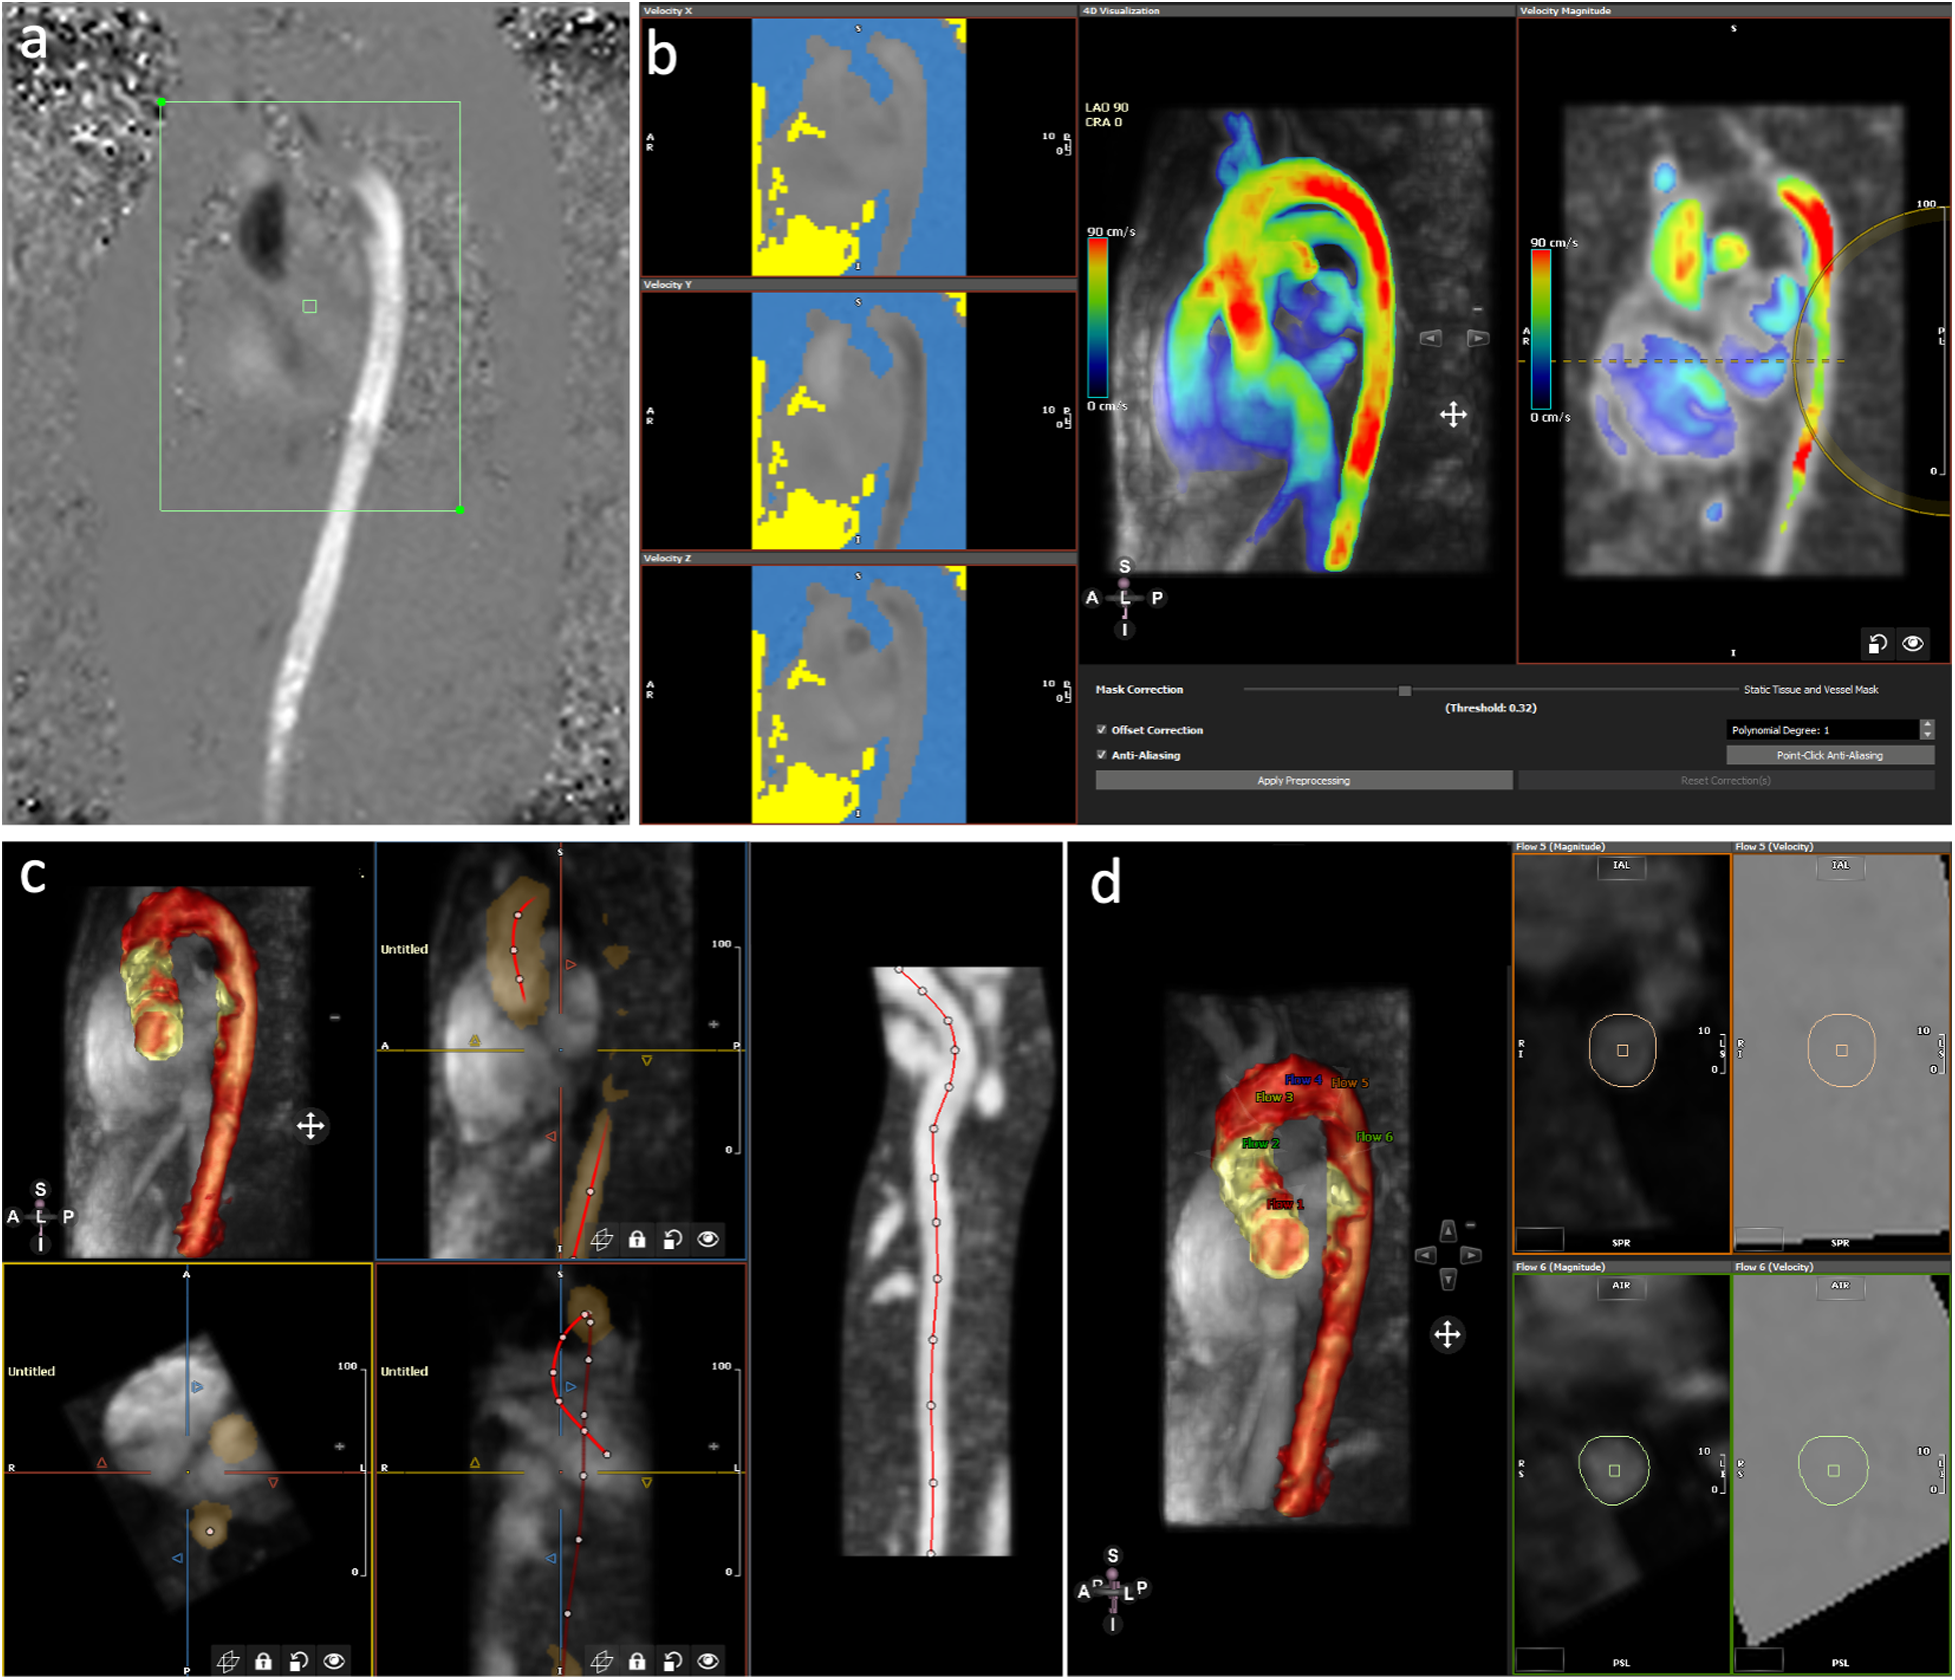

Figure 2

Post-processing of 4D flow CMR using software 2. (a) Selection of the area of interest of the acquired image. (b) Aliasing and background phase offset correction. (c) Placement of the vessel centerline along the thoracic aorta. (d) Positioning of the six analyses planes and manual correction of the lumen contour in every cardiac phase.